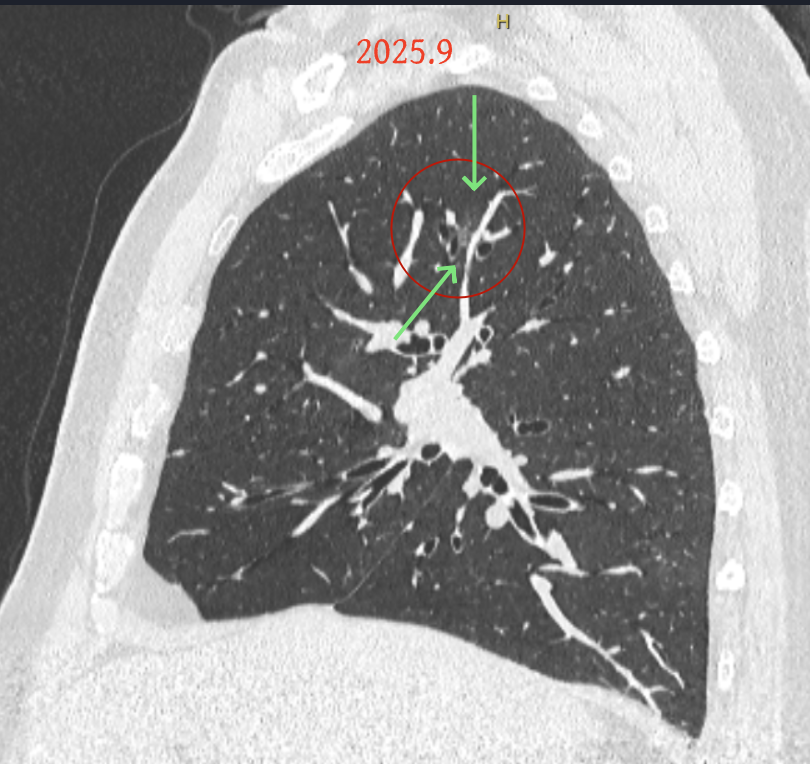

方形的是25年的,红色的主病灶,磨玻璃密度伴少许略偏高点密度,但还说不上典型混合磨玻璃病灶,考虑原位癌或微浸润性腺癌可能性大;蓝色的轮廓与边界欠清,位置靠上叶中央,无法段切或楔切;黄色的多发均淡而纯,分布在两肺。圆形粉色的是主要的两处23年时的样子,对比说不上很明显进展。鉴于若手术得切肺叶,何况两肺他处仍的结节,年纪又74了。我倾向保守点,先6-9个月复查,等进展并风险增加再来考虑怎么办的事。意见供参考!

病灶B似乎灶内有少许密度略偏高,但瘤肺边界欠清晰,总体说不上太显著的进展。

病灶没有确切纵隔窗可见的实性成分,但与血管关系较为密切。

病灶A以及他处磨玻璃结节其实进展都是不明显的,略与2022年比,病灶A稍显明显点。病灶B开始时极淡,之前进展虽有但也甚微,直到2025年9月仍是磨玻璃成分为主,只是点状少许密度稍高成分。但在最近半年内却显然进展!若从影像上判断,基本上就得是浸润性腺癌了。那有几点:一是必不能再随访;二是大小来看仍是1A期;三是从快速进展来说,可能含有部分高危亚型,比如微乳头或实体型等;四是他处的磨玻璃结节以及病灶A显然不能用病灶B的转移来解释,仍考虑是多原发早期肺癌。

这是较为少见的一个病例,磨玻璃为主,而且一直瘤肺边界欠清晰的病灶何以会在之前三年均极缓慢微小变化的情况下,近半年却快速进展呢?从影像细节上看,我们能否进一步分析哪种纯磨玻璃结节可能会较快进展?结合本例,我个人的考虑是:1、病灶整体显得是磨玻璃密度,但灶内并不均匀,就如磨玻璃密度中混入细沙状;2、整体轮廓虽然较清但瘤肺边界相对来说却并不太清晰;3、邻近有血管紧挨,而且与病灶这间缺乏间隙;4、病灶密度不高,没有明显实性成分,却有灶内有细支气管通气征,说明肿瘤成分具有收缩力,却与纯磨的收缩不匹配(纯磨一般不太会有明显收缩力)。如果有上面这些特征可能要提高警惕,一是适当较短的随访间隔,二是影像细节变化要更加注意,开始变化意味着已经进入发展期,而非蛰伏期。当然是否在2025年9月时定得手术了?如果是孤立性的病灶B,且位置位于能简单楔形切除的位置,那是可以考虑的。但位置深、两肺多发,切除范围不小,再今年据肺癌诊疗指南中说的混合磨玻璃结节实性成分不足25%是非侵袭性病变,且几乎不会转移,那么按原则仍再随访显然是可以的。本例的随访变化再次表明磨玻璃密度肺癌的诊疗个体化之路仍是很漫长的,按指南原则的随访或诊疗显然不足以覆盖所有病例,总结与经验积累永远在路上。